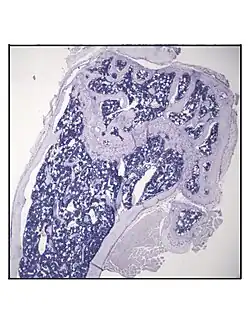

Representative distal femur histologic section of a 16-week-old healthy C57BL/6 mouse demonstrating a typical quantity of marrow adipocytes. -

Representative distal femur histologic section of a 16-week-old C57BL/6 mouse after 6 weeks of calorie restriction demonstrating an increased quantity of marrow adipocytes.